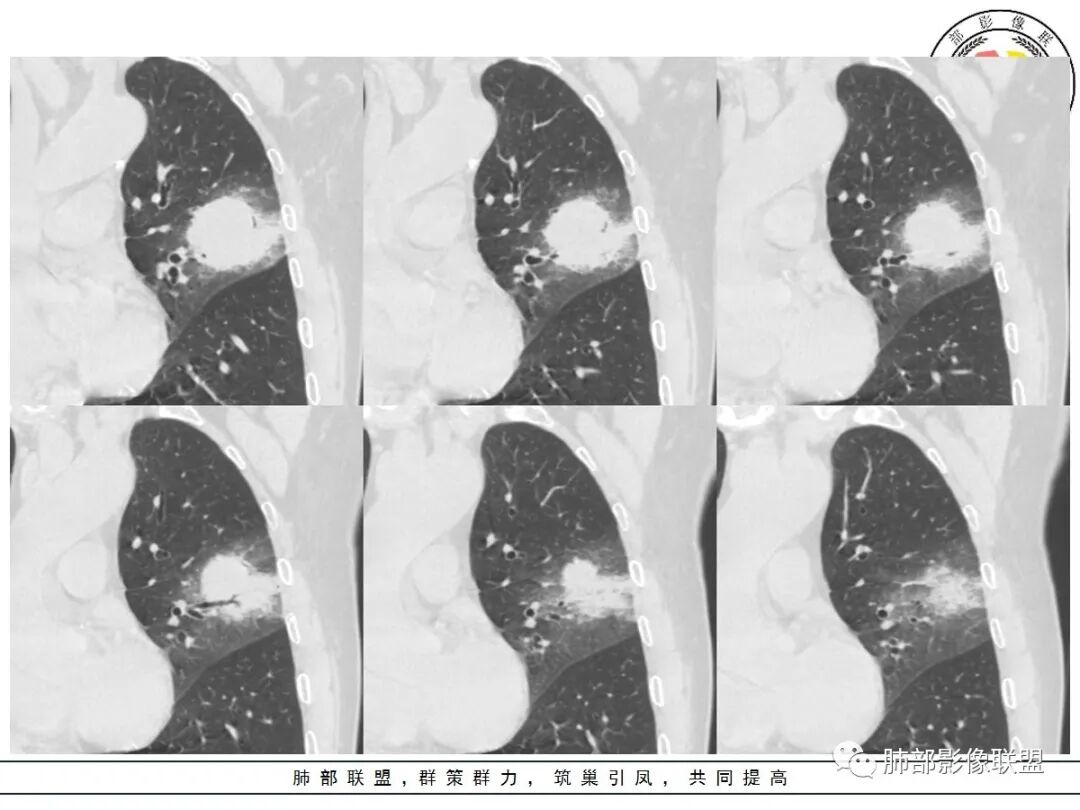

我标示一下,尖后段搭到一部分,前段也占了一点点。

主体在舌段

有占位效应吗?

有,斜裂局部膨隆

边缘膨隆,叶间裂有局部膨出下坠

有膨隆+收缩

密度?

实变为主,加周围模糊GGO

GGO+实变

强化如何?

强化有疑问,前面感觉有低密度的,有些图好像又均匀

不均匀中度强化

不均匀轻中度渐进强化。

整体形态

南边:

外围大,内带小

支气管?

支气管外面堵了,近端有扩张

有堵塞,有狭窄

中远端堵塞,堵塞端圆钝

炎性? 肺炎型肺癌待排

这个空洞的性质很重要,对最后诊断结果影响大,如果中间没有曲菌球,那就是偏心空洞,指向恶性,如果是曲菌球引起的新月形改变,那就不一定。至于到底是曲菌球还是偏心空洞,需要仔细看看强化情况。

不均匀性强化,远端坏死比较明显

如果强化明确,那就可以排除曲菌球。